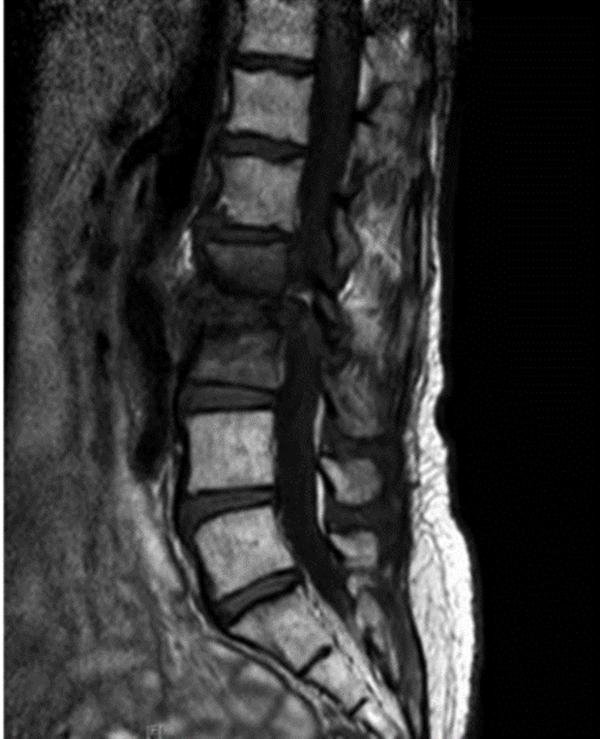

图3.核磁共振显像

腰椎MRI,L2和L3椎体强化,骨髓水肿,伴椎前/椎旁软组织肿胀,弥漫性椎间盘膨出,黄韧带增厚,椎管狭窄

腰椎MRI,L2/3明显狭窄,左侧明显,伴椎间盘炎和中度硬膜囊压迫,周围可见软组织水肿,左侧腰大肌轻度水肿。